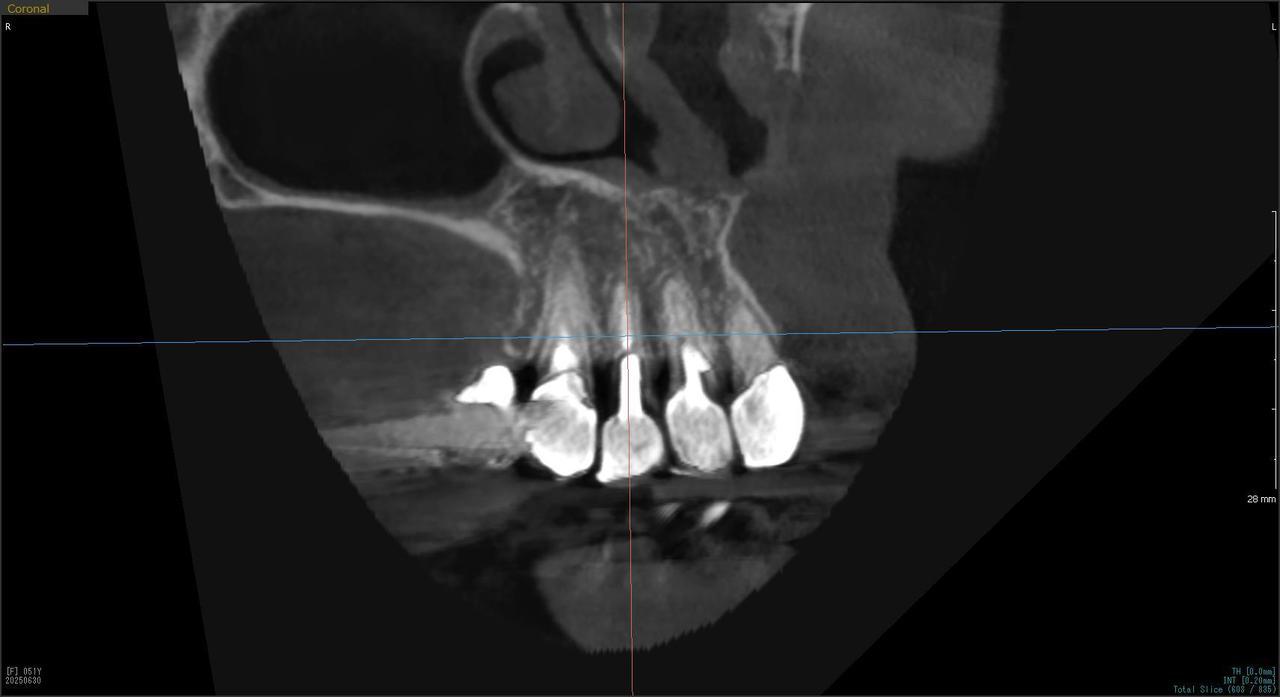

Before

枚方市のインプラントの症例

I・K 様 女性 40代

症状としては、左上5の歯根破折を起こしていたため、排膿と自発痛をみとめた。それにともなう骨の大きな欠損。

治療法としては、炎症が強くたったためと、炎症による頬側側歯肉の退縮を認めていたために、まず、抜歯を行い上顎洞内及び歯抜した周囲組織の回復を試みた。その後、患者様がインプラント治療を希望したため、薄い上顎骨に対しては、グラフトレスサイナスリフト、骨欠損部には、人口骨補填を行い、頬側歯肉が退縮していることを改善するために、1回法でリーリングアバットメントを装着して、アバットメントの上に歯肉が覆うようにして、歯肉のボリューム回復を行った。2か月後、インプラントが骨と結合していることを確認して、光学印象を行い、2週間後にアバットメントとジルコニアクラウンを装着した。

治療結果としては、大幅な骨欠損があったが、グラフトレスサイナスリフトと骨欠損部に人工骨を補填して、抜歯した穴が自然に治る状態にしたことで、2か月半という短い期間での治療を完了することができた。(仮に、GBRや通常のサイナスリフトでの治療を行っていたら、最低でも1年は、かかってくる治療であると考える。)また、今回は、即時荷重を避け、1回法での治療を行ったことで、噛めない期間ができてしまったが、1回法で行ったことにより、歯肉のボリュームが増して、ブラッシングがしやすい口腔内環境にすることができた。低侵襲で、短時間で、治療を終えることができ、また、審美性・機能性の回復も行えたことができた。

治療の期間・回数:約2.5か月、6回

治療の価格:368,500円(税込)

治療費の内訳:インプラント基本料(フィックスチャー及び手術費用、投薬費用、レントゲン費用、インプラント上部費用(アバットメントおよびジルコニアクラウンの費用用)330000円(税込み)。オプション費用グラフトレスサイナスリフト費用プラス人工骨費用 38500円(税込み

治療のリスクや副作用:手術後に、痛みや腫れ、出血、合併症などを引き起こす可能性があります。噛む感覚がご自身の歯と異なる場合があります。見た目がご自身の歯と異なる場合があります。手術後にメインテナンスを継続しないと、インプラントが抜け落ちる可能性があります。